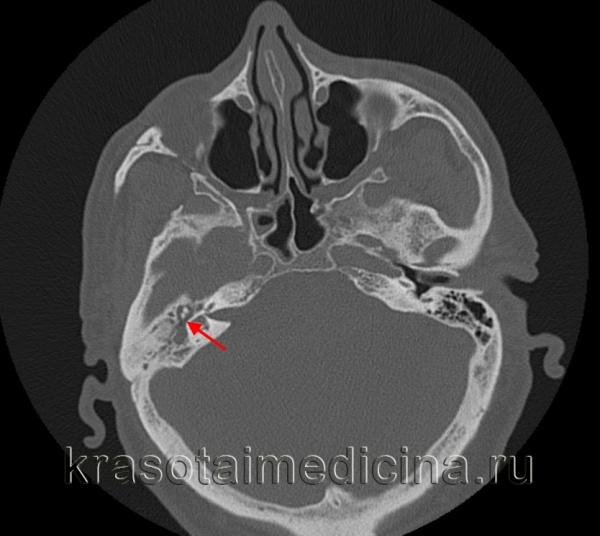

- Рентгенография, КТ височных костей. С целью оценки распространенности деструкции костных тканей и проведения дифференциальной диагностики назначается рентгенография височной области по Шюллеру и Майеру. При низкой информативности полученных рентгенограмм показана компьютерная томография височных костей в аксиальных и коронарных проекциях с шагом в 1-2 мм.